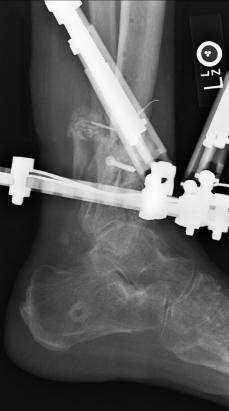

Postoperative (13th) images of left ankle

The image(s) displayed here were created following Liam's 13th surgery which was performed by Dr. Saunders. After a few hiccups getting

the surgery scheduled, Liam spent most of the September 13th afternoon in his 13th surgery. ;-) The surgery lasted about 5 hours and according

to the doctor, it was a good surgery. The 1st photo shows the new frame bracing that holds Liam's ankle together. The next series of photos show

various angles of the ankle and the rods that go from the frame into and through the left ankle. There was some concern that the swelling would

burst and allow for infection. Looks like we are now past that concern. Liam is still on antibiotics to ward of potential infection. The flesh

images show how the skin reacts to having the leg adjusted by the brace. The doctor has had to cut the skin to allow the rods to move freely.